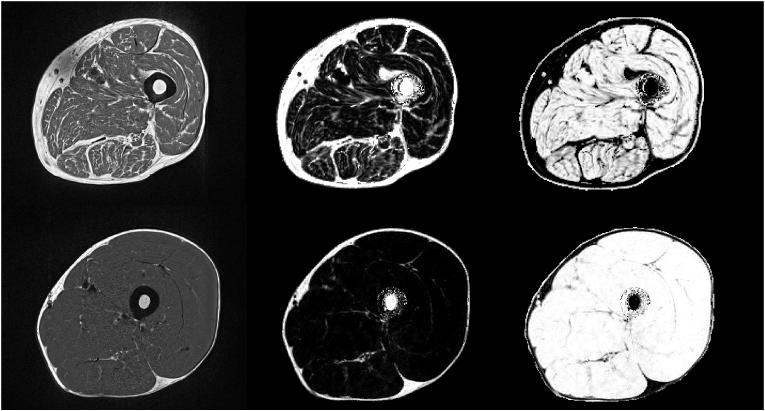

Magnetic resonance imaging (MRI) is the dominant 3D imaging modality to quantify muscle properties in skeletal muscle disorders, in inherited and acquired muscle diseases, and in sarcopenia, in cachexia and frailty.

MRI technology provides a rich toolset to assess muscle deterioration. In addition to classical measures such as muscle atrophy using T1 weighted imaging and fat infiltration using Dixon sequences, parameters characterizing inflammation from T2 maps, tissue sodium using non-proton MRI techniques or concentration or fiber architecture using diffusion tensor imaging may be useful for an even earlier diagnosis of the impairment of muscle quality.

磁共振成像(MRI)是用于量化骨骼肌疾病、遗传性和获得性肌肉疾病、肌肉减少症、恶病质和虚弱症中肌肉特性的主要三维成像方式。

MRI技术提供了一套丰富的工具来评估肌肉退化。除了使用T1加权成像测量肌肉萎缩和使用狄克逊序列测量脂肪浸润等经典方法外,通过T2 mapping表征炎症的参数、使用非质子MRI技术测量组织钠含量或使用扩散张量成像测量浓度或纤维结构,可能有助于更早诊断肌肉质量受损情况。